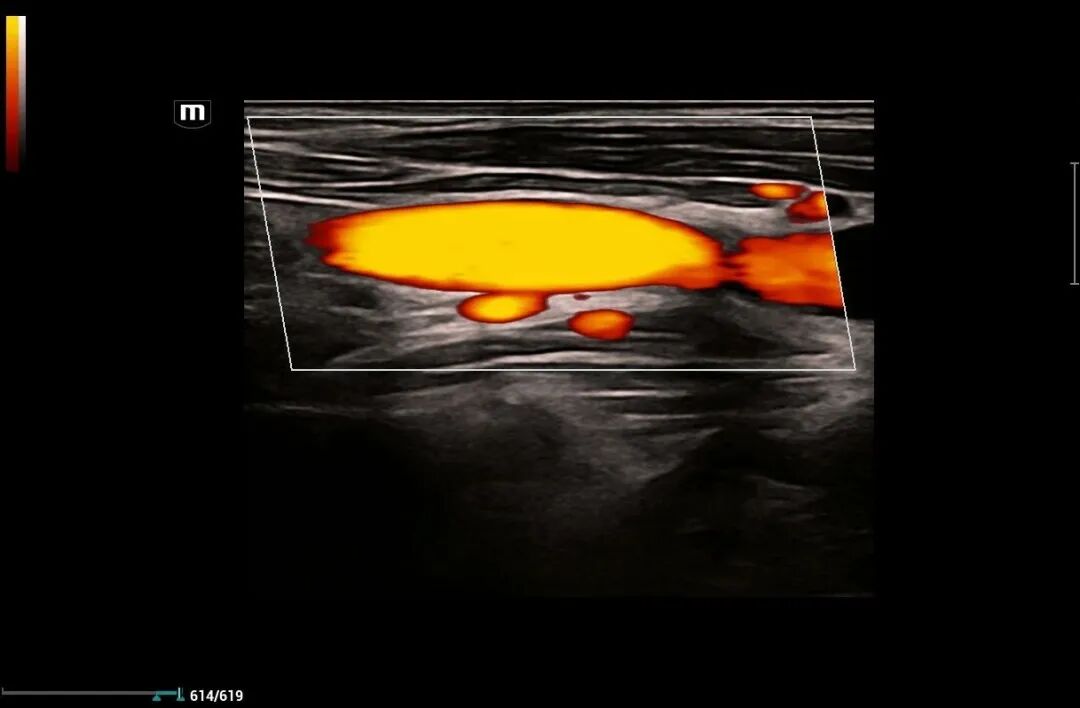

为进一步提高我院诊疗检查与诊断水平,不断满足城乡患者日益增长的就医需求,健全和完善医疗保障体系。2022年12月我院引进了mindray- Resonal9T高端彩色多普勒超声系统正式投入使用,此设备具备超声介入、超声造影、超声高帧率 STE 剪切波弹性成像及应变式弹性成像(甲状腺、乳腺、肝脏),二维、三维、四维、阴式、盆底、心脏及血管超声等功能。此设备的引进标志着海伦影像学科将跨越新的高度,以此助力城乡百姓解决看病难,看病贵的就医难题!

2.肢体血管。如上、下肢动脉,深浅静脉检查;动静脉炎、动脉硬化、动静脉栓塞等。